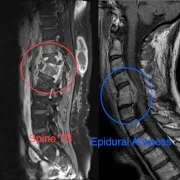

– Spine Tumors

We offer safe and advanced spinal tumor surgery in Thane for the removal of both benign and malignant spinal tumors. Our neurosurgeons use microsurgical and minimally invasive techniques to ensure maximum tumor removal while preserving spinal stability and nerve function. With integrated care including diagnosis, surgery, and rehabilitation, we ensure the best possible outcomes for spinal tumor patients.